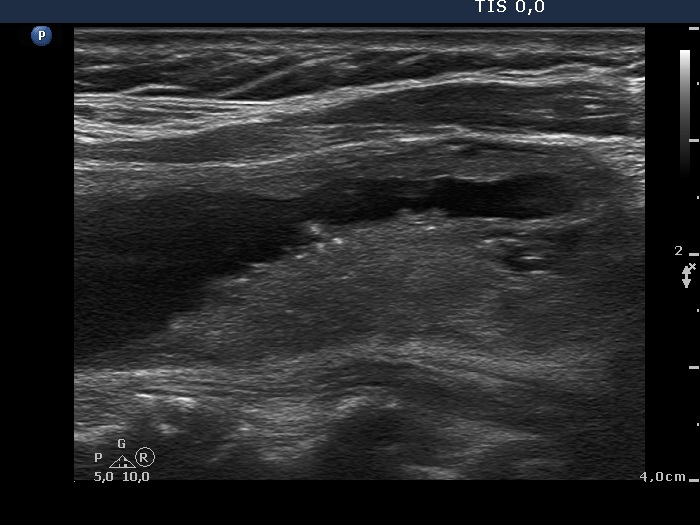

Benign cystic degeneration (cytological diagnosis) - case 662

The bright figures marked with arrows at the border of the cystic and solid part (right side of the nodule in the right image) can be easily misinterpreted as punctate echogenic foci (microcalcifications); these are posterior back wall enhancements caused by the microcystic area ventral to them.

There are comet-tail artifacts within the cystic fluid with a broader than usual tail.